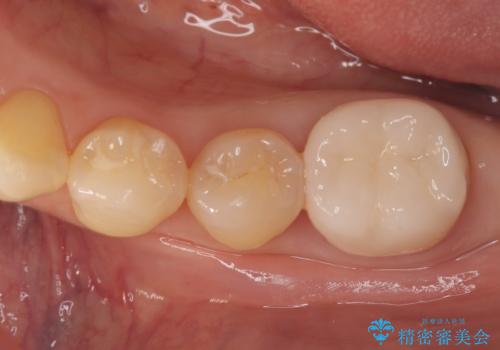

欠けやすい大きなプラスチック充填から、耐久性の高いセラミッククラウンへ

担当医 河口智英